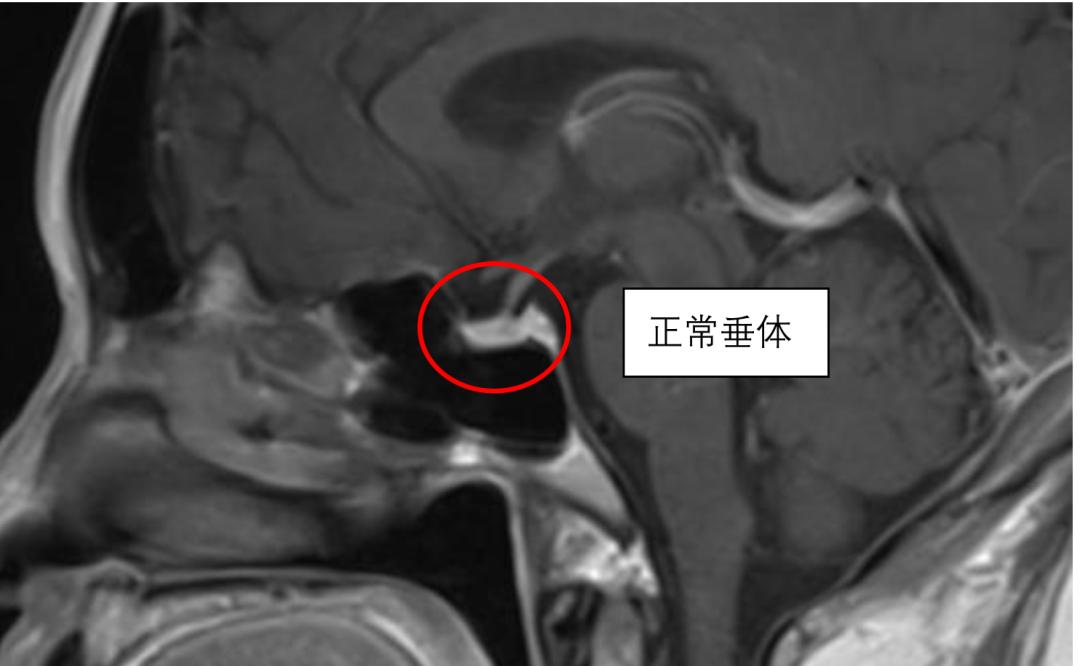

杨主任介绍道,垂体是一个内分泌腺体,可以分泌激素。它长在大脑底部的中间位置,上方是视交叉,两侧是颈内动脉,形状大小类似于花生米。下丘脑便是通过垂体来调节机体的内分泌系统,垂体的病变往往会影响到内分泌系统的紊乱。